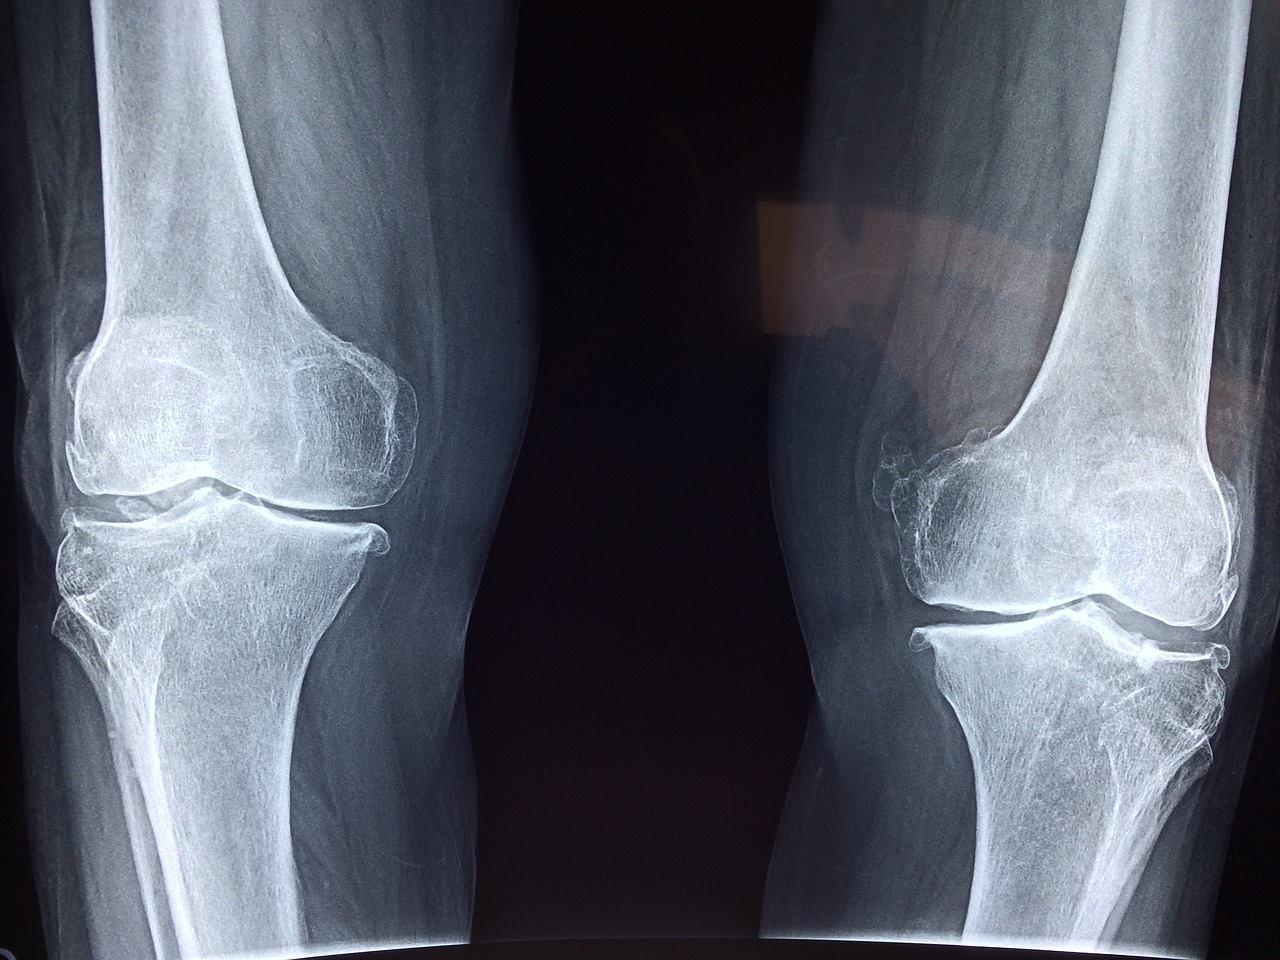

- 작은 충격에도 쉽게 골절

- 골다공증 환자는 넘어지거나 가벼운 충격에도 쉽게 골절이 발생합니다.

- 특히 손목, 고관절(엉덩이뼈), 척추가 골다공증으로 인한 골절이 많이 발생하는 부위입니다.

- 고관절 골절은 회복이 어렵고 활동성을 크게 제한할 수 있어 주의해야 합니다.